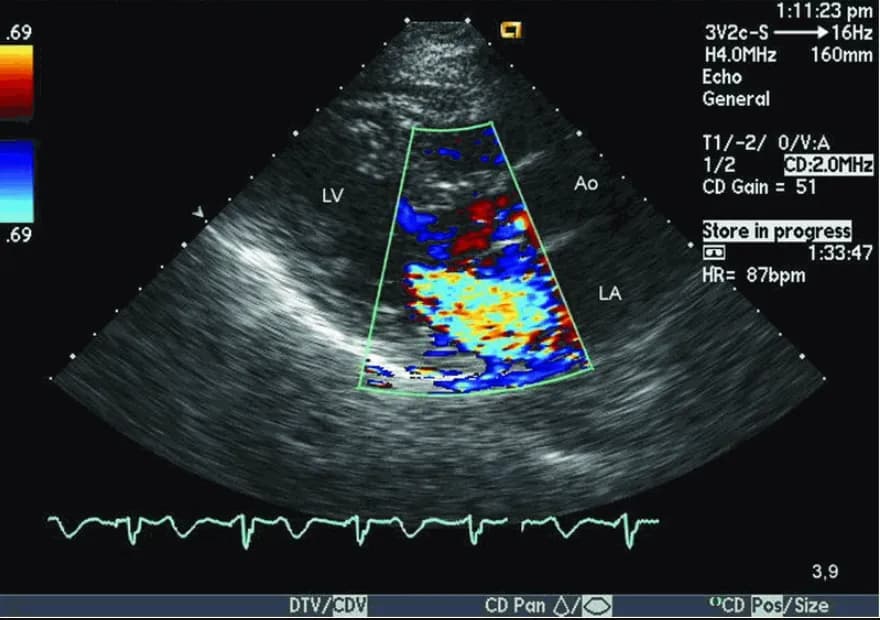

Siêu âm tim Doppler cho thấy hở van hai lá.